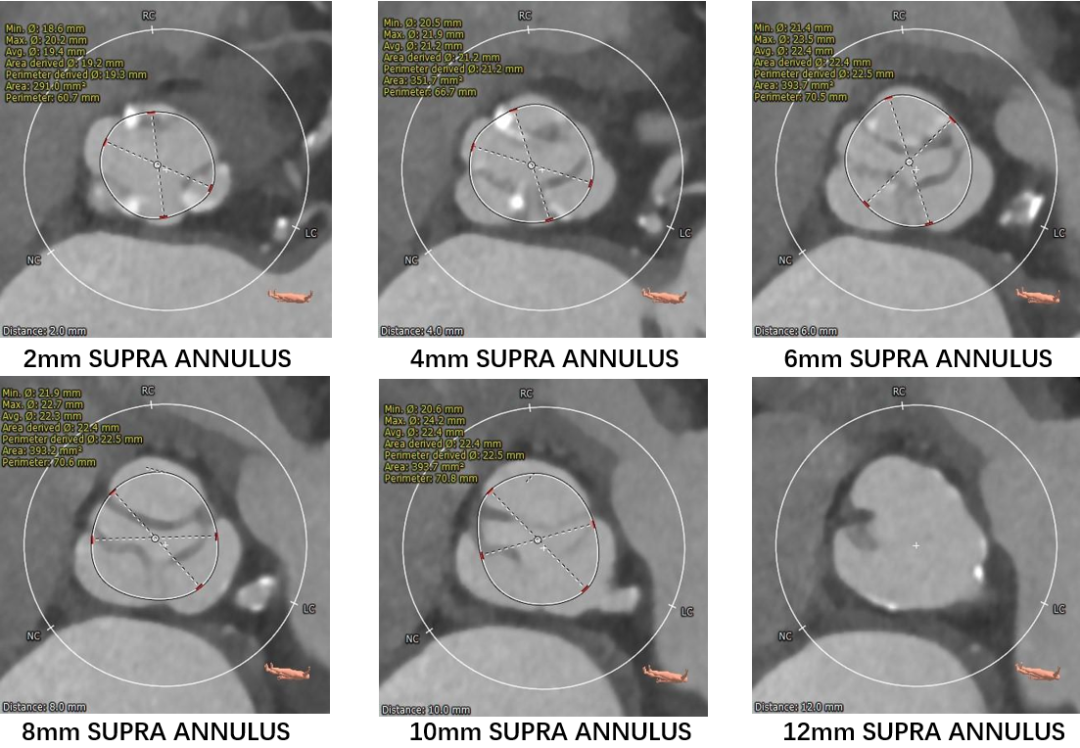

瓣环上测量